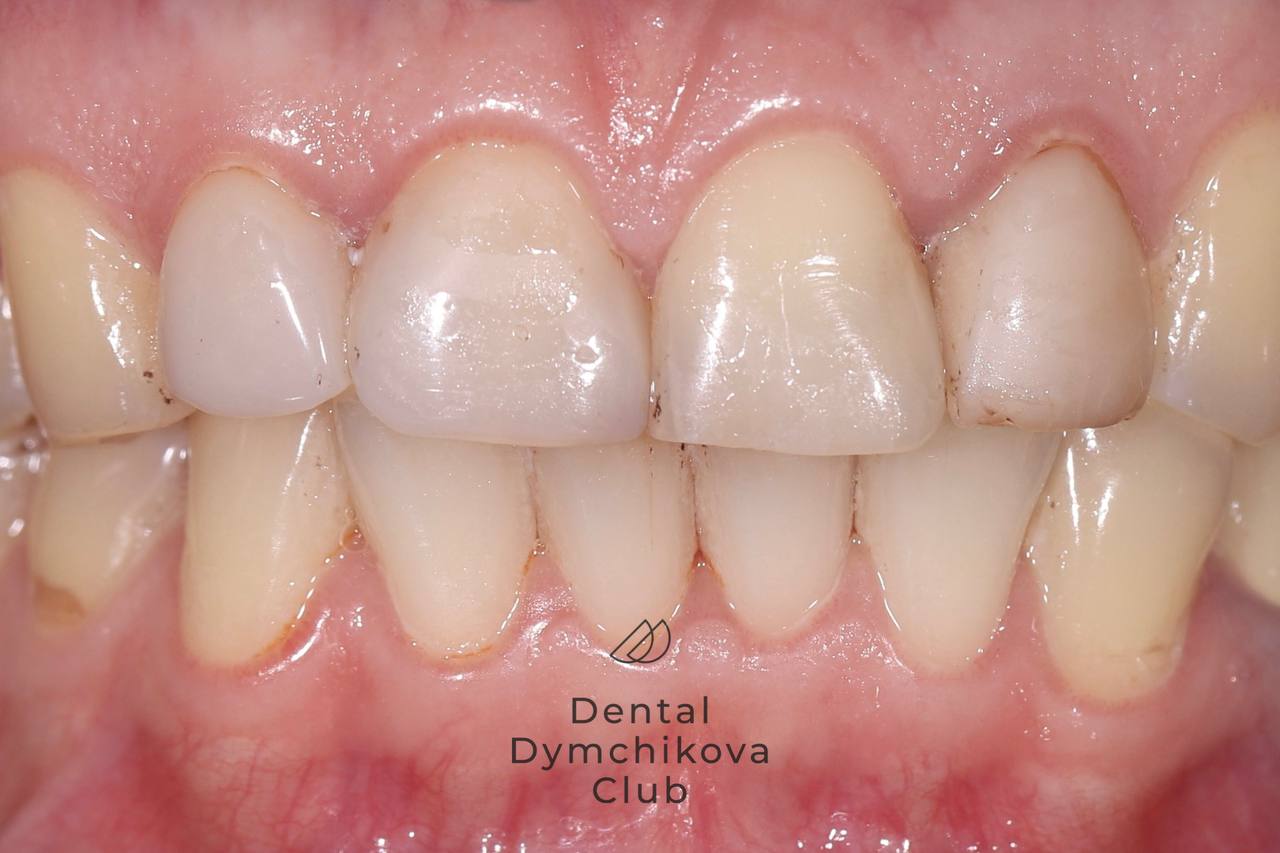

Виниры

Пациентка, 46 лет.

Жалобы: на некрасивые передние пломбы, застревание нитей между зубов.

Пациентка каждые 5 лет меняла пломбы, доктор порекомендовал поставить виниры для долгосрочного результата.

Лечение: установка трех виниров E-max и одной коронки E-max.

Срок лечения: 2 недели (2 посещения).

Доктор: Дымчикова Анна Вавиловна